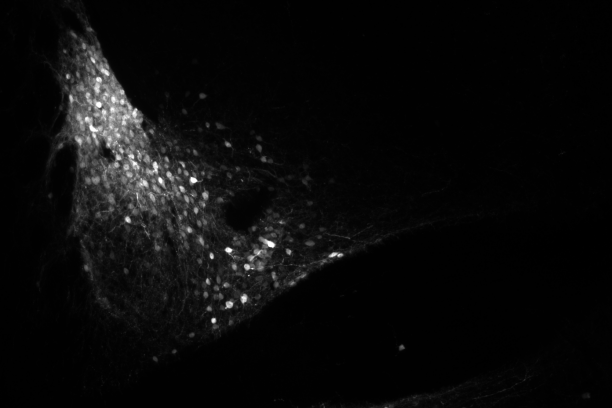

Sudden unexpected death in epilepsy (SUDEP), the enigmatic pathology whereby epileptic patients are found to have died without another cause, is the most frequent cause of death in epilepsy patients. The rare cases of SUDEP in healthcare settings show a sequence where apnea precedes terminal cardiac arrhythmias, implicating death due to respiratory decline. From our work and the work of others, it is clear that the amygdala has an underappreciated role in breathing. Our research aim is to investigate these brain regions through multidisciplinary approach to determine their role in epilepsy, apneas, and SUDEP.